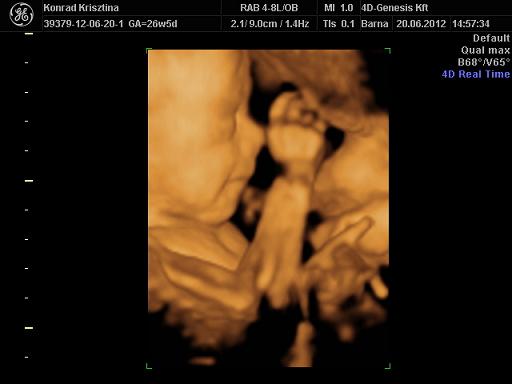

tegnap 4d:

minden rendben, fejvégű, de a lábával frankón betámaszt néha az oldalamba. lepény még mélyen fekvő :( egy héttel kisebb 860g a becsült súlya. tutira lány és bazi izmoska :) olyan válla van, mint aki gyúr, kerek és szálkás. ja és pisze mint a fiúk...